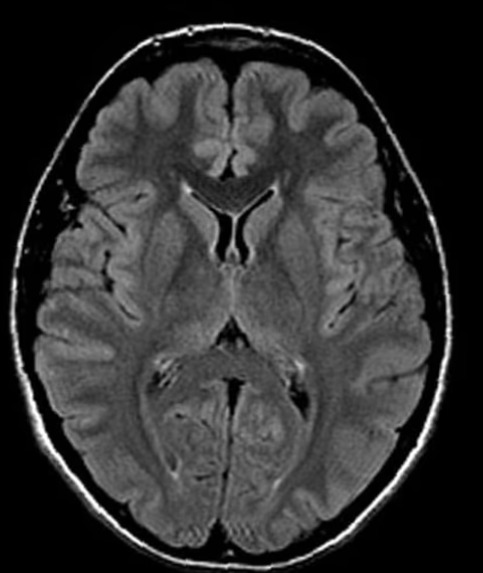

脑部MRI第二意见

- 白质病变 — 它们意味着什么?

- 多发性硬化MRI第二意见

- 高级神经影像脑部MRI复查 · 复杂神经系统病例

- 复杂脑部病变诊断明确化

多发性硬化与白质病变